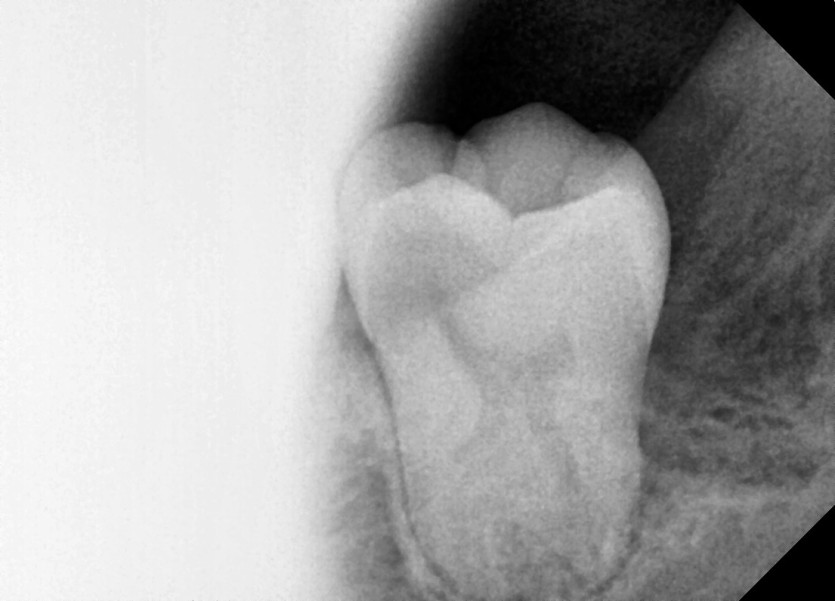

#38,48 사랑니 발치

구강 외과 전문의가 당일 발치했습니다.